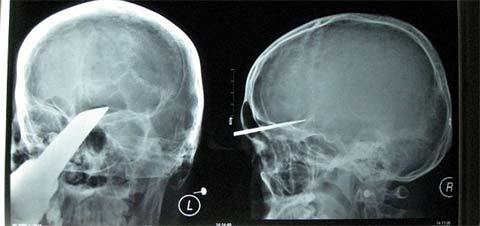

Cậu bé này chắc chắn phải đau đầu "như búa bổ" sau khi bị một thanh kiếm đâm

sâu 5cm vào sọ.

Tai nạn xảy ra khi Zhang Bin đang chơi đùa cùng các bạn tại nhà. Cậu bé 15 tuổi

này đã được đưa đến bệnh viện lập tức nhưng các bác sĩ ở đó không thể điều trị

cho cậu.

Sau đó, Bin được chuyển sang một bệnh viện khác cách đó 400km ở Hồ Nam, Trung Quốc.

Các bác sĩ đã đưa Zhang tới phòng phẫu thuật và thanh kiếm được lấy ra trong một

ca mổ kéo dài 4 giờ đồng hồ.

"Thật may mắn, thanh kiếm không chạm vào các động mạch trong hộp sọ và các dây

thần kinh chủ chốt, nếu không thì đó sẽ là một câu chuyện khác", trưởng ca phẫu

thuật nói.

Zhang Bin được cho là sẽ phục hồi hoàn toàn.